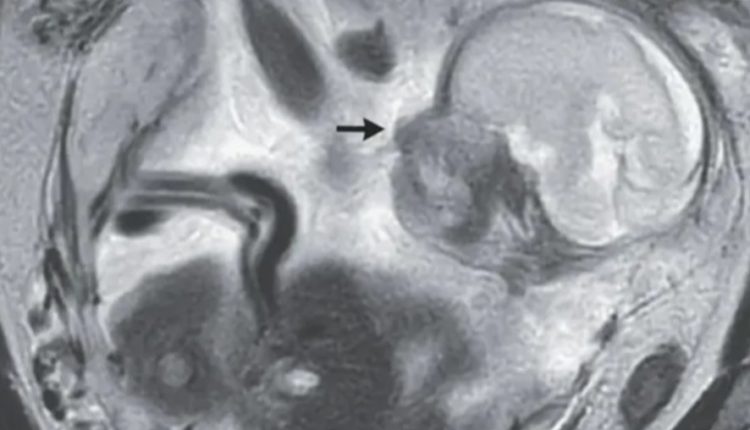

இத்தகைய அசாதாரண கர்ப்பம், தாய்க்கு ஆபத்தை ஏற்படுத்தக்கூடும். மேலும் இந்த பிரித்தானிய பெண்ணுக்கோ, கரு முட்டைக்குழாயில் கூட குழந்தை வளரவில்லை, அது அவரது வயிற்றுக்குள் வளர்ந்திருந்தது.

அதாவது, உணவுக்குழாயின் ஒரு பகுதியான வயிற்றுக்குள் அந்த குழந்தை வளர்ந்திருந்ததைக் கண்டு மருத்துவர்கள் அதிர்ச்சியடைந்தார்கள்.

அதுவும், அவர்கள் அந்த பெண்ணை பரிசோதனை செய்யும்போது, அது ஆறுமாதக் குழந்தையாக வளர்ந்து விட்டிருந்தது. கர்ப்பப்பைக்கு வெளியே வளரும் குழந்தையால், தாயின் உயிருக்கு ஆபத்து என்பதால், உடனடியாக அறுவை சிகிச்சை மூலம் அந்த குழந்தையை தாயிடமிருந்து பிரித்துவிட்டார்கள்.